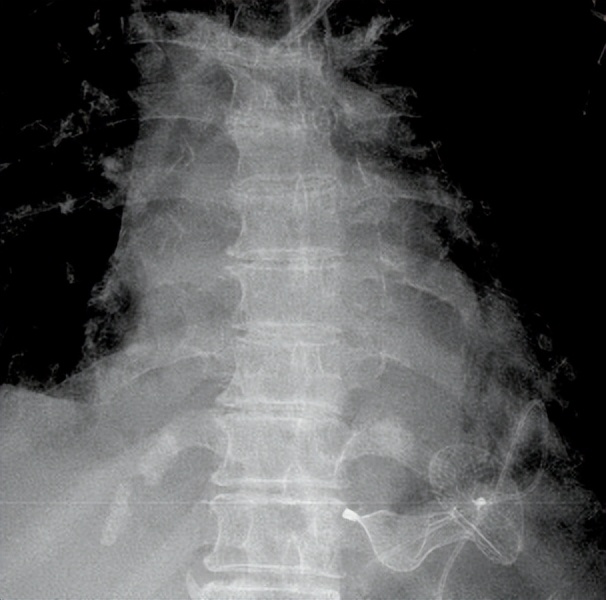

术后复查胸片显示封堵器位置稳定

术中首先经皮建立ECMO,行左心室造影见室间隔近心尖多发性大缺损,遂经股动脉、主动脉、左心室、室间隔穿孔处、右心室、右心房、上腔静脉、右颈内静脉成功建立轨道,再经颈内静脉沿轨道钢丝顺利送入输送鞘及封堵器成功实施封堵。术后心脏彩超及造影显示封堵器位置稳定,残余少量分流,右室及肺动脉压力明显降低,达到预期治疗效果。术后患者血流动力学稳定,即刻撤除了ECMO。术后当天拔除气管插管,次日转回普通病房。患者术后恢复顺利,症状明显改善,无严重并发症发生,术后两周康复出院。